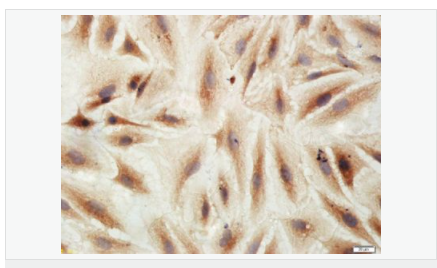

| 產品應用 | WB=1:500-2000 IHC-P=1:100-500 IHC-F=1:100-500 Flow-Cyt=3ug/test ICC=1:100-500 IF=1:100-500 (石蠟切片需做抗原修復) not yet tested in other applications. optimal dilutions/concentrations should be determined by the end user. |

| 細胞定位 | 細胞膜 |